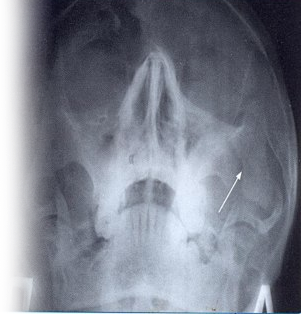

Рентгенография скуловой кости – важный метод прицельного исследования, который позволяет оценить целостность скуловой кости.

Показание для проведения рентгена скуловой кости:

• подозрение на перелом;

• подозрение на наличие очаговых образований скуловой кости.